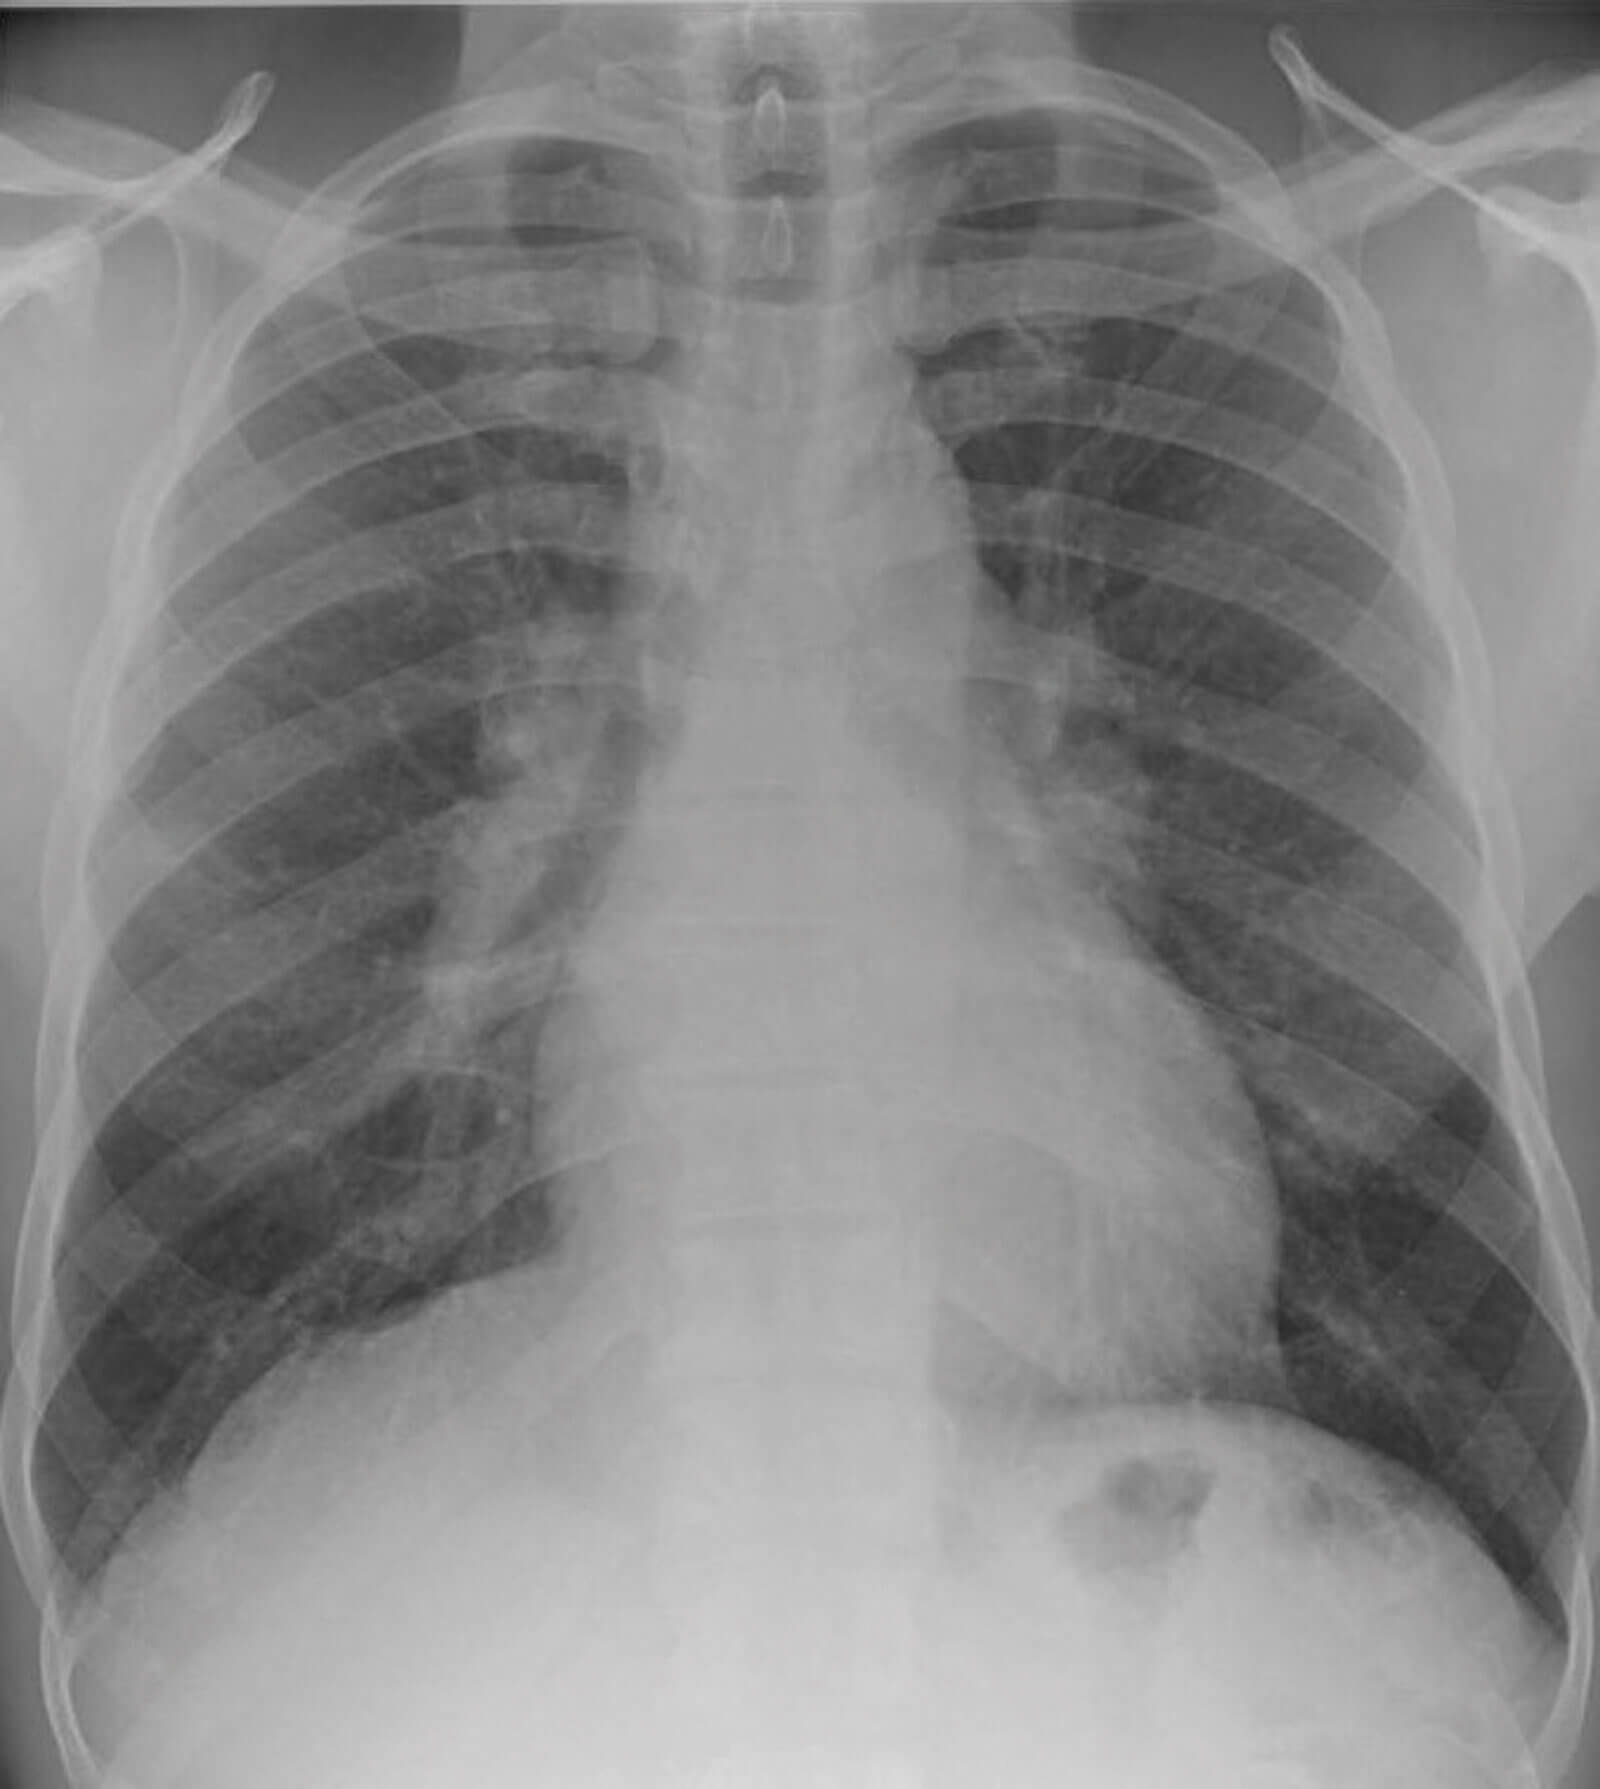

Figure 1: Chest x-ray showing bilateral hilar prominence.

The concurrent presentation of AAU and left facial nerve palsy resulted in the consideration of Heerfordt-Waldenström syndrome (HWS) amongst the differential diagnosis. Upon further screening, the patient reported a one-month history of unintended weight loss, frequent rigours and night sweats. A subsequent chest x-ray demonstrated the strong possibility of bilateral hilar lymphadenopathy (Figure 1) and blood tests revealed an elevated serum ACE levels at 85 (normal range 20-70) and positive anti-nuclear antibodies (ANA). His T-Spot test was negative.